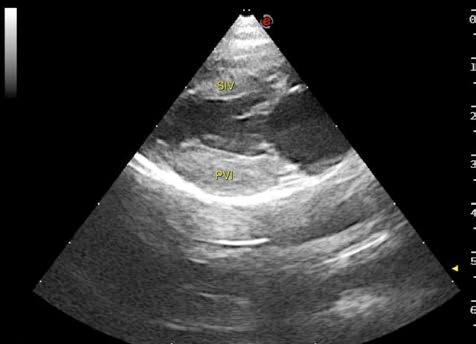

Issuu converts static files into: digital portfolios, online yearbooks, online catalogs, digital photo albums and more. Sign up and create your flipbook.